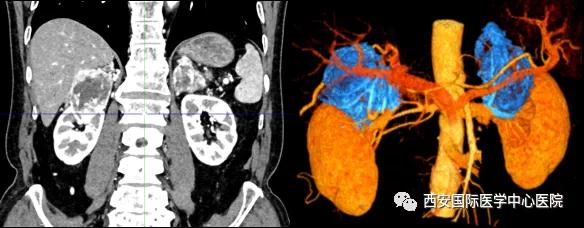

今年七十五歲的患者,來自陜西省商洛市,四月前因腰背部疼痛就診于當(dāng)?shù)蒯t(yī)院,行CT檢查發(fā)現(xiàn)“右腎、雙側(cè)腎上腺占位,前縱膈淋巴結(jié)腫大,雙肺多發(fā)結(jié)節(jié)、胸椎骨質(zhì)破壞,考慮轉(zhuǎn)移瘤”。為進(jìn)一步診斷治療,患者的兒子帶他來到西安某三甲醫(yī)院,查泌尿系CT提示“右腎占位性病變,多考慮腎癌,雙側(cè)腎上腺多發(fā)轉(zhuǎn)移灶,腹膜后多發(fā)腫大淋巴結(jié)”;行穿刺活檢提示“腎透明細(xì)胞癌”;并給予患者口服靶向藥物的治療方案。

自四月份至今,患者一直口服靶向藥物治療(阿昔替尼5mg 2次/日),期間無不良反應(yīng),目前腰背部疼痛癥狀也有所緩解,復(fù)查影像學(xué)資料提示瘤體較前縮小,腫瘤完整切除的可能性明顯提高;而且患者的兒子也是一名外科醫(yī)生,所以他更想為父親完成后續(xù)的手術(shù)治療。

患者一家慕名前來到西安國(guó)際醫(yī)學(xué)中心醫(yī)院找到楊增悅教授。楊增悅教授仔細(xì)看完患者的之前的影像學(xué)及病理資料后,診斷為:右腎透明細(xì)胞癌(T4N1M1);并安排他住院。而后,主管醫(yī)生及時(shí)為他完善了術(shù)前檢查及評(píng)估。7月15日,在麻醉手術(shù)中心柴偉主任、王彬榮副主任、李娟護(hù)士長(zhǎng)、李瑞剛護(hù)士長(zhǎng)及全體麻醉手術(shù)中心團(tuán)隊(duì)的有力保障下,成功完成了這臺(tái)“大”手術(shù)。

手術(shù)由楊增悅教授主持,舒濤主治醫(yī)師、王東主治醫(yī)師主刀,黃怡醫(yī)師、王平醫(yī)師協(xié)助完成。由于第四代達(dá)芬奇機(jī)器人更加靈活和精準(zhǔn)的特性,手術(shù)全程順利,尤其是完全精準(zhǔn)的“解鎖”了右腎動(dòng)脈和右腎靜脈的數(shù)十根交互纏繞的分支血管。術(shù)后患者麻醉恢復(fù)后生命體征平穩(wěn),順利返回泌尿外科普通病區(qū)進(jìn)一步康復(fù)。